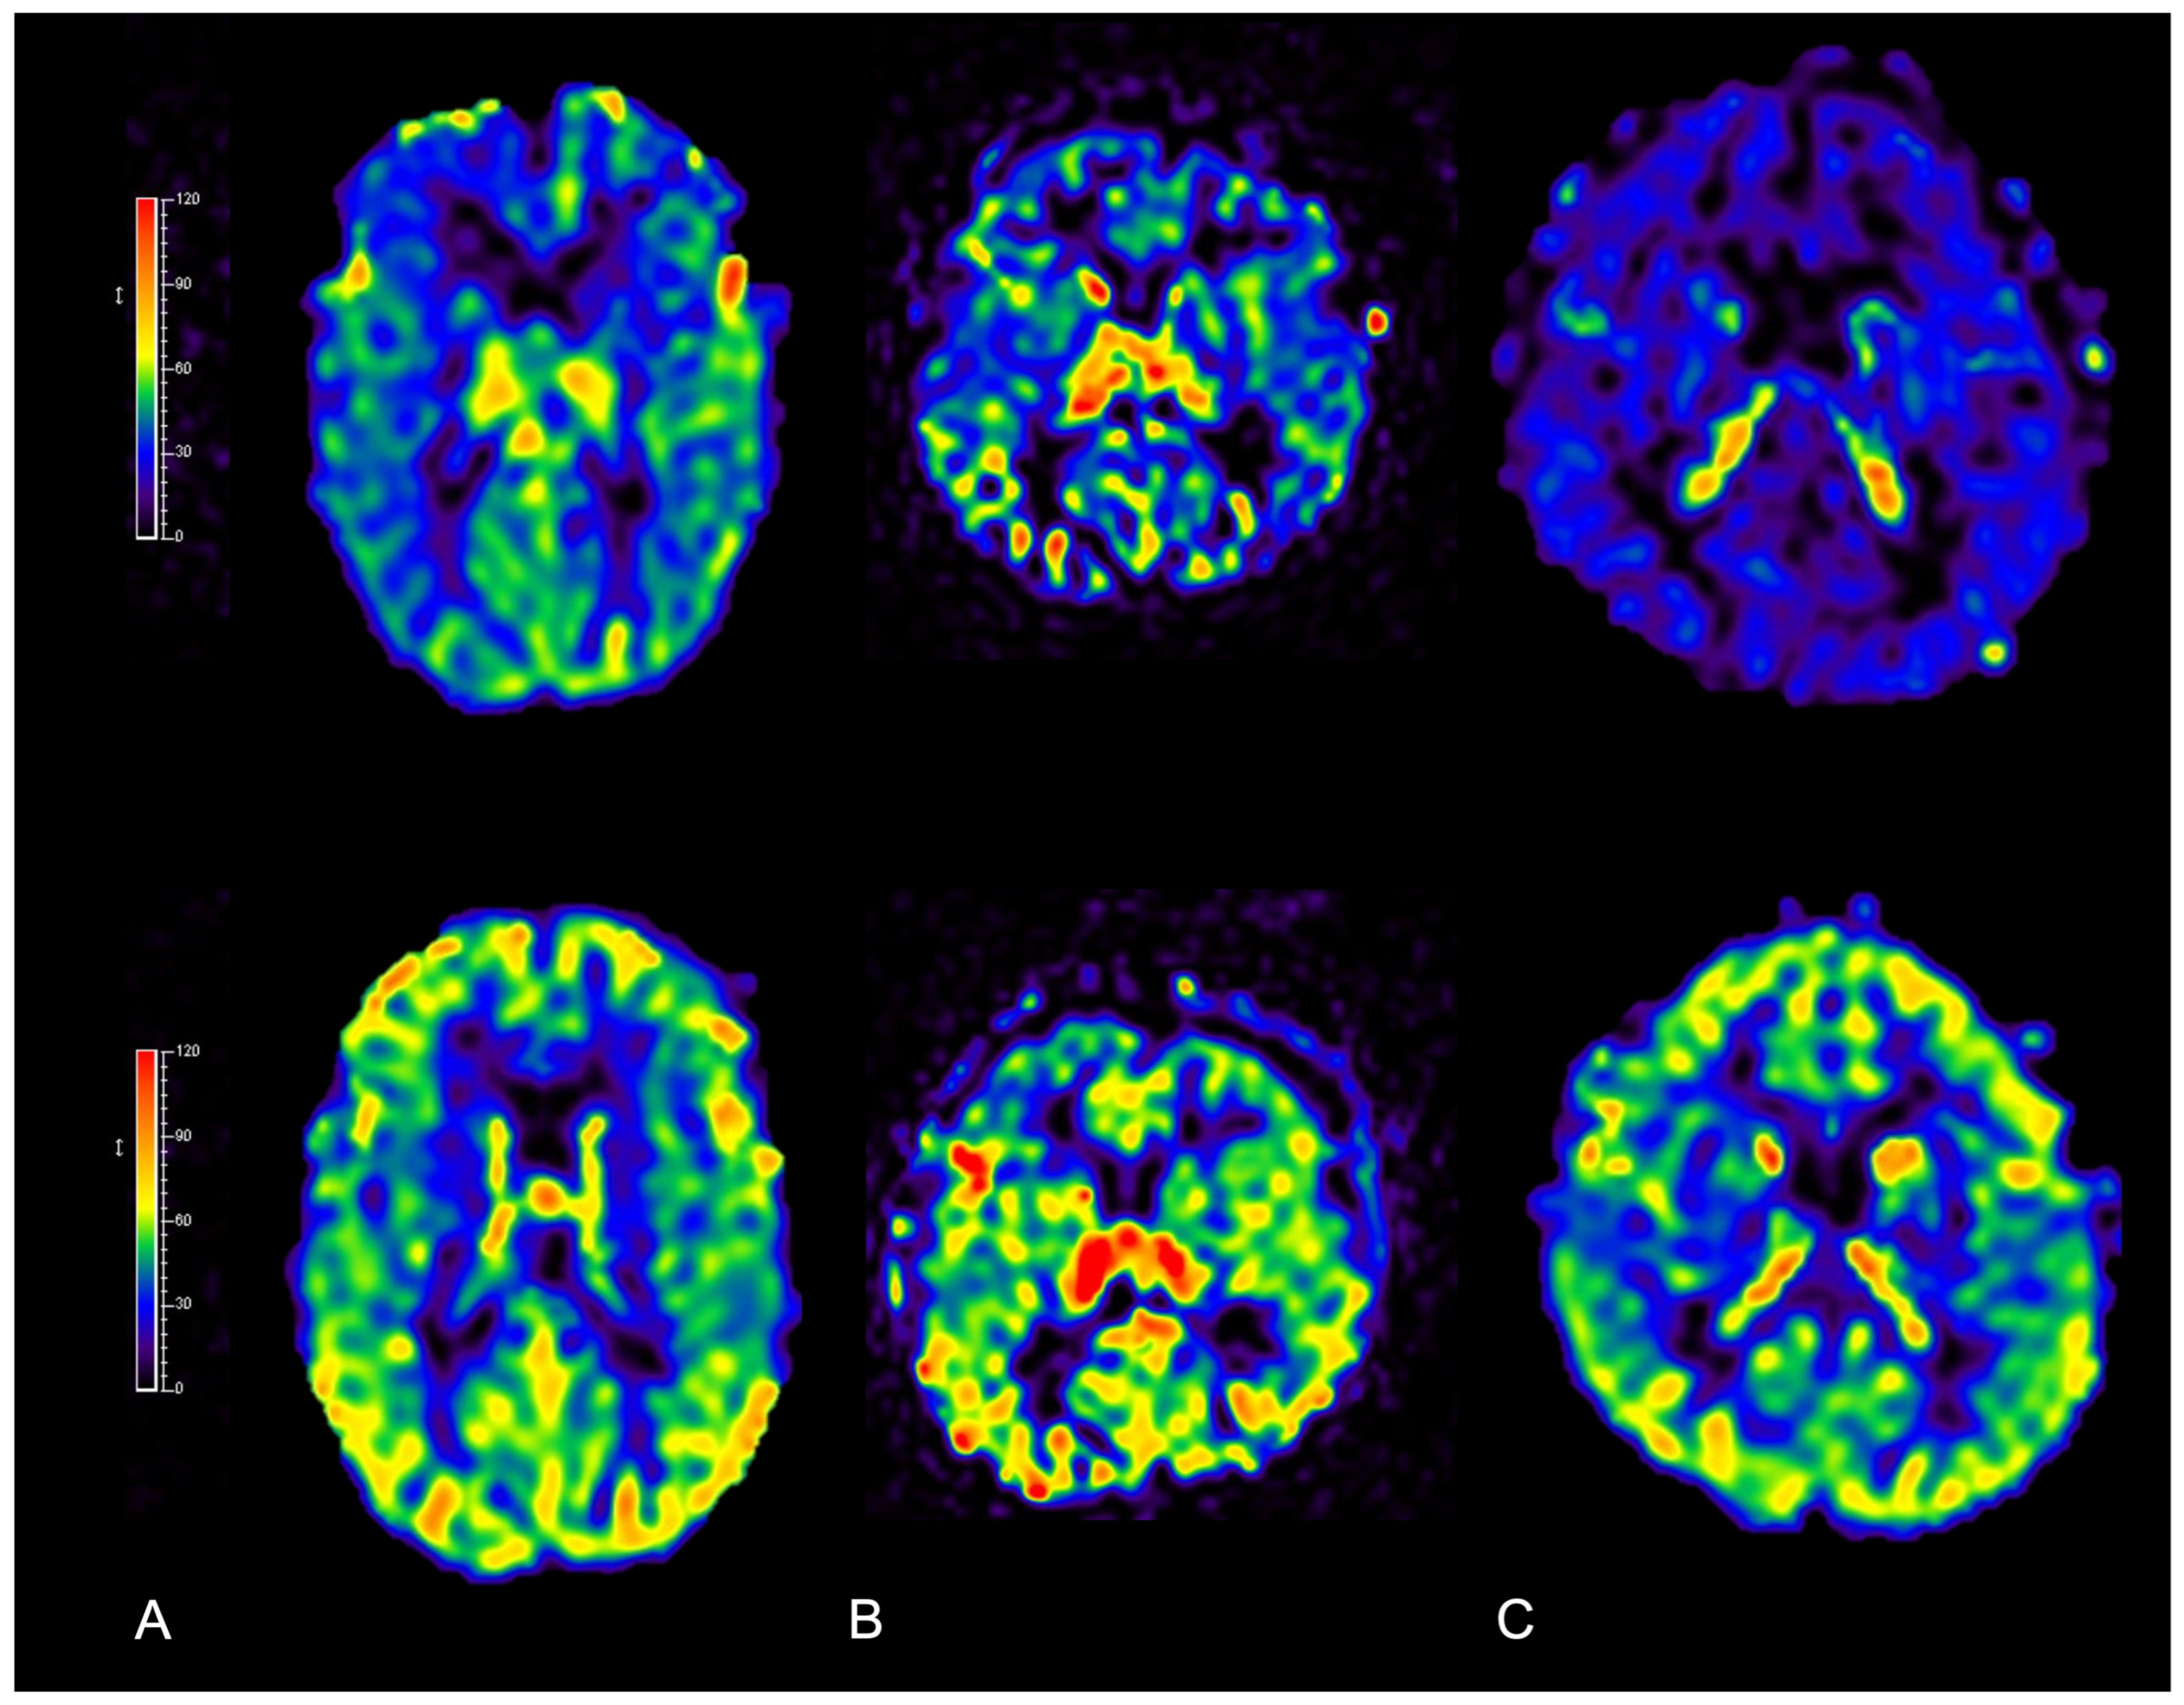

- Rijken, B.; Leemans, A.; Lucas, Y.; van Montfort, K.; Mathijssen, I.; Lequin, M. Diffusion tensor imaging and fiber tractography in children with craniosynostosis syndromes. Am. J. Neuroradiol. 2015, 36, 1558–1564. [Google Scholar] [CrossRef]

- Sun, A.H.M.; Eilbott, J.; Chuang, C.M.; Yang, J.F.M.; Brooks, E.D.M.; Beckett, J.M.; Steinbacher, D.M.M.; Pelphrey, K.; Persing, J.A. An Investigation of Brain Functional Connectivity by Form of Craniosynostosis. J. Craniofacial Surg. 2019, 30, 1719–1723. [Google Scholar] [CrossRef] [PubMed]

- de Planque, C.A.; Gaillard, L.; Vrooman, H.A.; Li, B.; Bron, E.E.; van Veelen, M.-L.C.; Mathijssen, I.M.; Dremmen, M.H. A Diffusion Tensor Imaging Analysis of Frontal Lobe White Matter Microstructure in Trigonocephaly Patients. Pediatr. Neurol. 2022, 131, 42–48. [Google Scholar] [CrossRef]

- de Planque, C.A.; Florisson, J.M.G.; Tasker, R.C.; Rijken, B.F.M.; van Veelen, M.L.C.; Mathijssen, I.M.J.; Lequin, M.H.; Dremmen, M.H.G. A diffusion tensor imaging analysis of white matter microstructures in non-operated craniosynostosis patients. Neuroradiology 2022, 64, 2391–2398. [Google Scholar] [CrossRef] [PubMed]